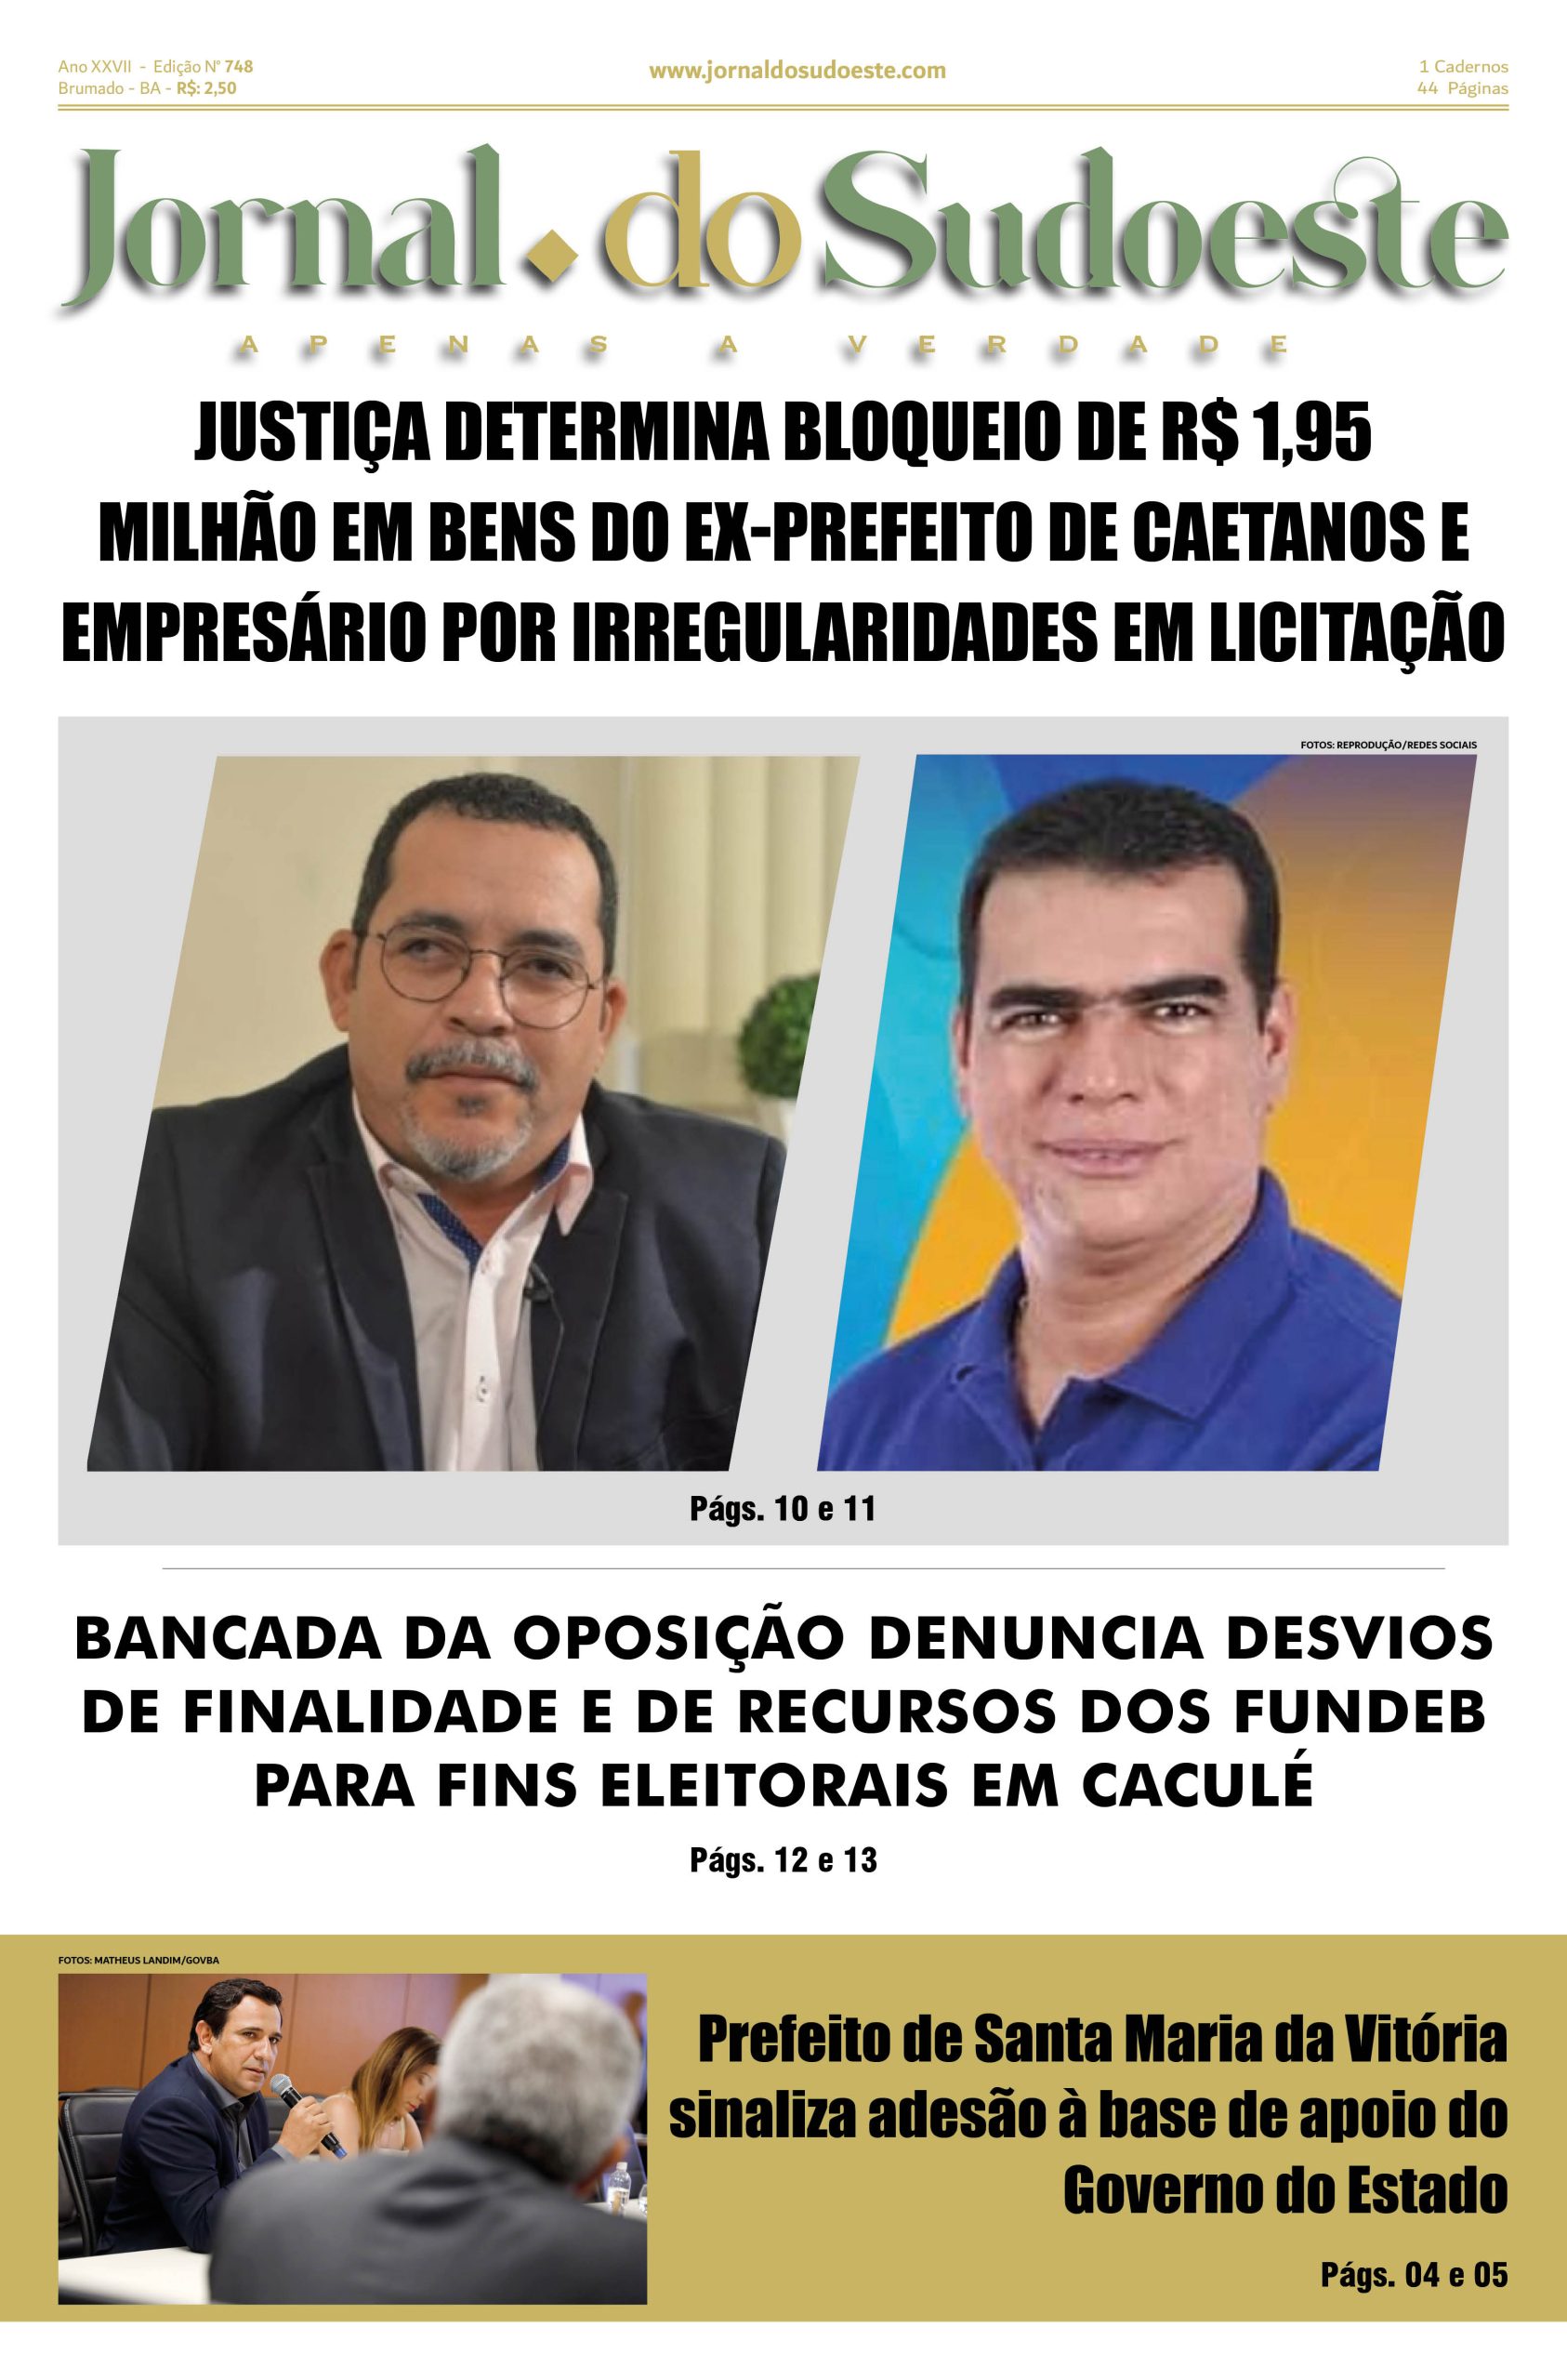

![O Presidente Luiz Inácio Lula da Silva e a Ministra da Saúde, Nísia Trindade, anunciaram ontem a produção - em larga escala - da primeira vacina 100% nacional e de dose única contra a dengue.

A previsão é que, a partir do próximo ano, sejam ofertadas inicialmente 60 milhões de doses anuais.

Segundo a Ministra, espera-se vacinar, em dois anos, toda a população elegível [de 2 a 59 anos]”.

Ao se referir às fases de testes clínicos de imunizantes, Nísia esclareceu que “por enquanto, os idosos ainda não poderão tomar a vacina porque, enquanto são testadas, há sempre um cuidado com essa população”.

Segundo o Governo Federal, a partir de uma parceria entre o Instituto Butantan e a Chinesa WuXi Biologics, a produção em larga escala da vacina 100% nacional e de dose única contra a dengue se dará por meio do Programa de Desenvolvimento e Inovação Local do Ministério da Saúde, já aprovado e em fase final de desenvolvimento tecnológico.

Com informações da Agência Brasil, visite o nosso portal para conferir a notícia na íntegra.

www.jornaldosudoeste.com

Repórter: @ticinha100

Até mais!](https://scontent-cdg4-3.cdninstagram.com/v/t51.71878-15/482038570_502936576182440_929714912930447734_n.jpg?stp=dst-jpg_e35_tt6&_nc_cat=110&ccb=1-7&_nc_sid=18de74&_nc_ohc=2Y3WJUsvpUEQ7kNvwFlIY_S&_nc_oc=Adk6q5Hc_5AsO4-EWHx3JwBy3T6wmSYxrORIKGq9OLddJAdk4f2gIhVITRHiMjPZCK4&_nc_zt=23&_nc_ht=scontent-cdg4-3.cdninstagram.com&edm=ANo9K5cEAAAA&_nc_gid=_h3qU4b_aWfj4dPJ_TZGAA&oh=00_AfGpJ7o3A-_8p34hXRVGBqcLlzvIluVYvOmxCRJUXCcJ1g&oe=681494AE)